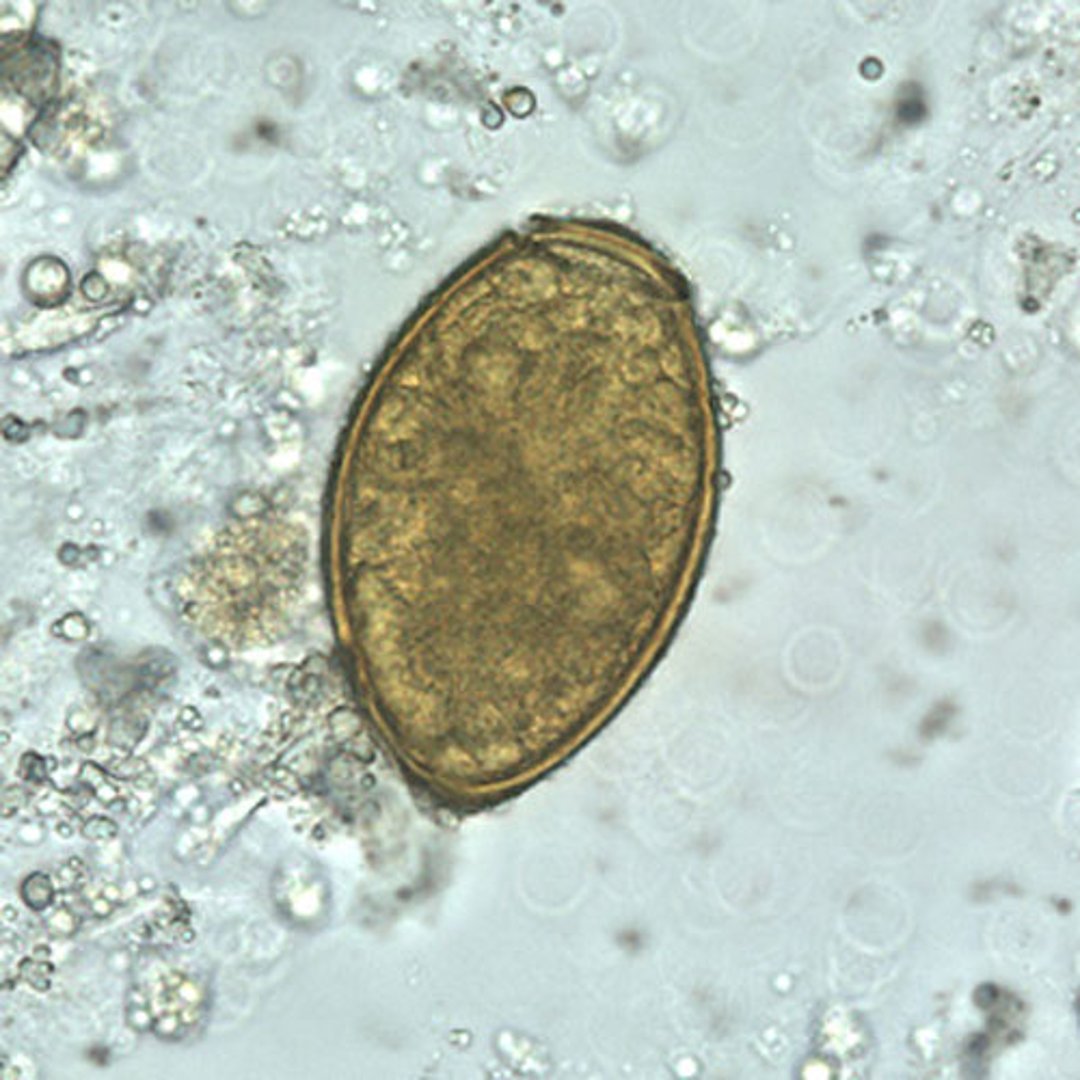

Paragonimus westermani(卫氏并殖吸虫)卵

卫氏并殖吸虫虫卵长度在80至120微米,宽度在45至70微米。它们呈黄褐色,卵形或长形,外壳厚实。这些卵通常不对称,一端略微扁平。在较大的一端,卵盖清晰可见。无卵盖端增厚

虫卵在痰液或粪便中排出时未形成胚胎。